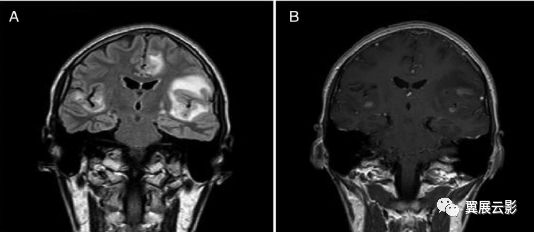

1、垂体腺瘤:大多见于15岁以后患者,常有典型的双颞侧偏盲,视神经萎缩及内分泌改变。X线检查示蝶鞍扩大,鞍底破坏,钙化少见,肿瘤位于鞍内。CT呈等或高密度肿块影,边缘清楚,呈分叶状,瘤内出血为高密度,无钙化,增强不如脑膜瘤明显,但囊变机会多。MRI示等T1、等T2信号,并发出血示T1高信号。微腺瘤尚未强化呈低信号。垂体上缘膨隆,垂体柄移位,是诊断垂体瘤的间接征象。

(垂体腺瘤)

(垂体ACTH-PRL细胞腺瘤)